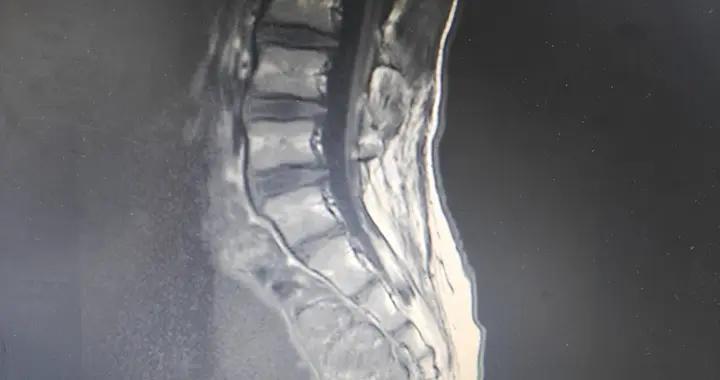

男性肌肉量會以每年約1%的速度流失,進入老年期還可能加速。伴隨而來的還有骨密度下降,這共同導致力量減弱、容易疲勞、平衡能力變差,跌倒骨折的風險大增。